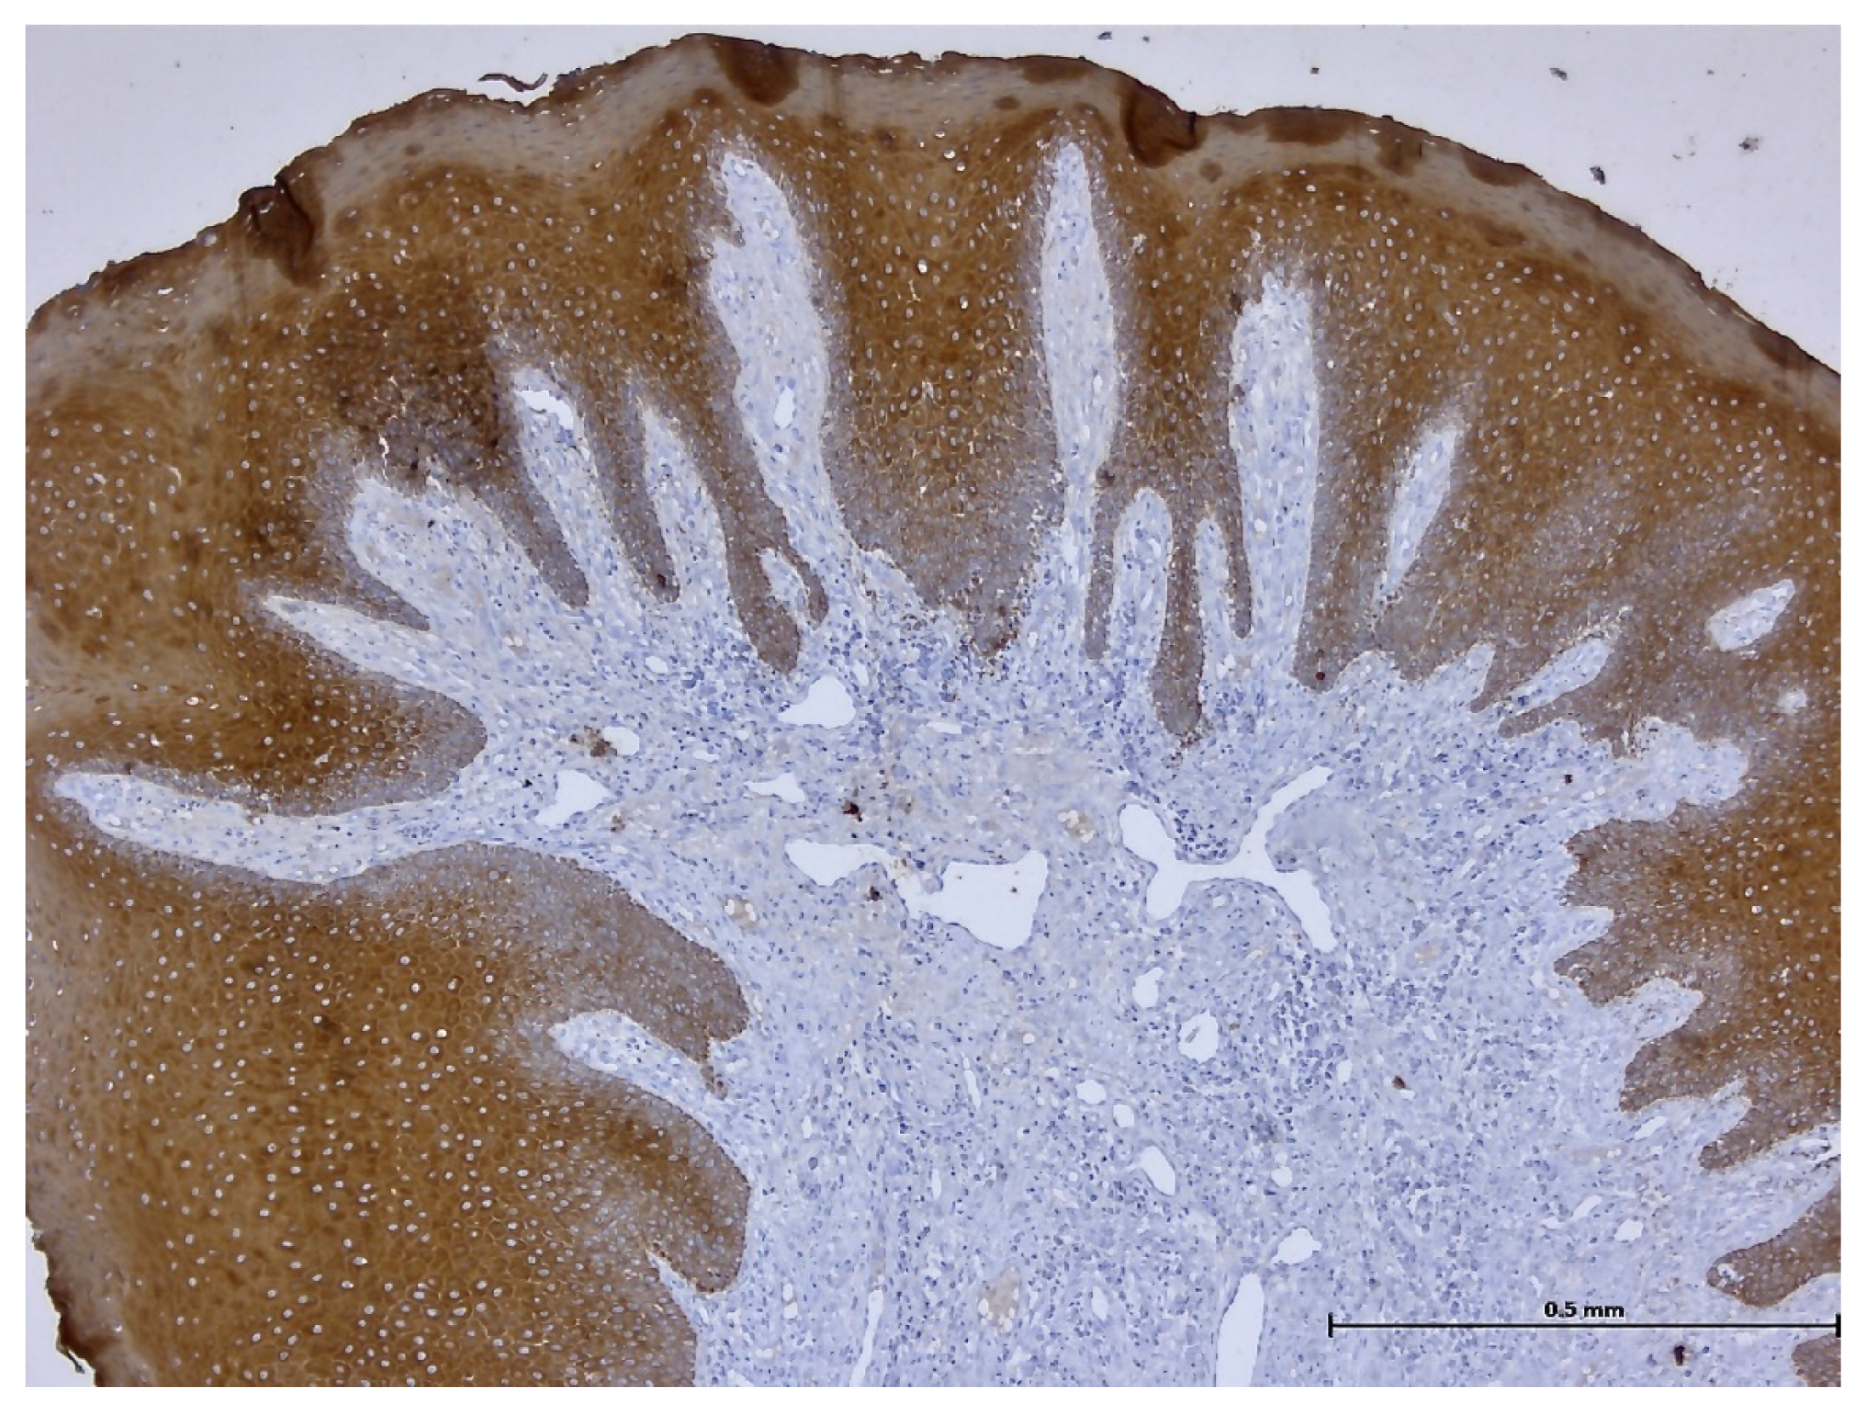

3. Results